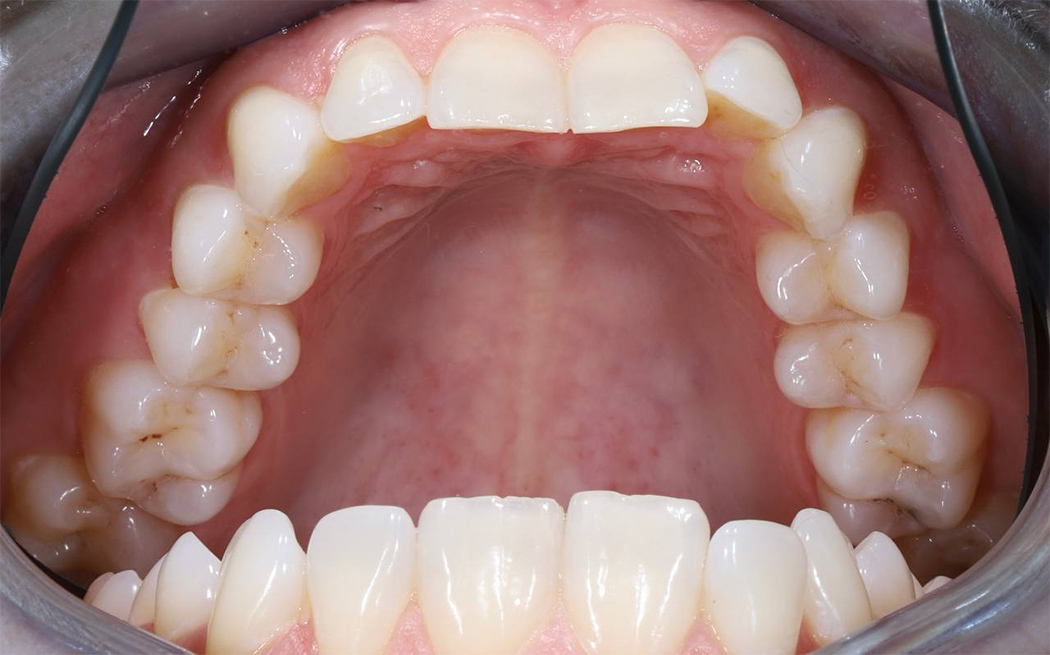

Исправление неправильного прикуса и замена устаревших реставраций для гармоничной улыбки